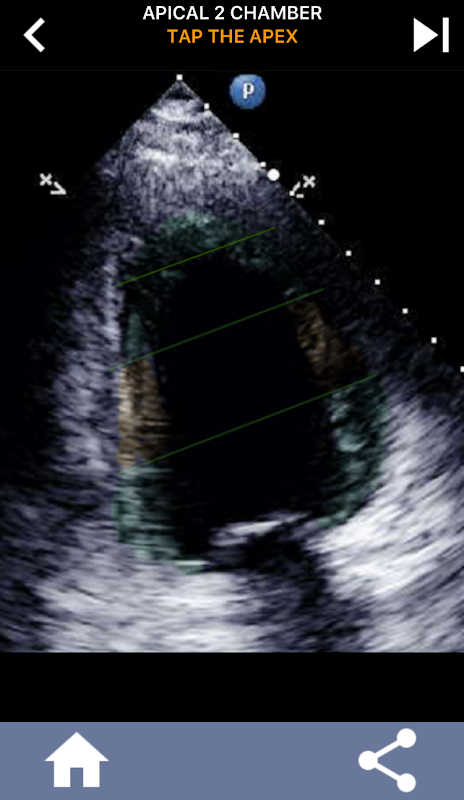

Diese App enthält alle Echoansichten, die das AHA-segmentierte Myokard anzeigen, und fragt Sie, ob Sie das richtige Segment antippen möchten. Ich persönlich finde, dass sich wiederholendes Quiz am besten für mich eignet, wenn ich das Thema schnell lernen / auswendig lernen muss. Wenn Sie ein Ultraschall-Student sind, der Echo / TTE studiert, ist dies meiner Meinung nach eine hervorragende Ergänzung zu Ihrem Studium.